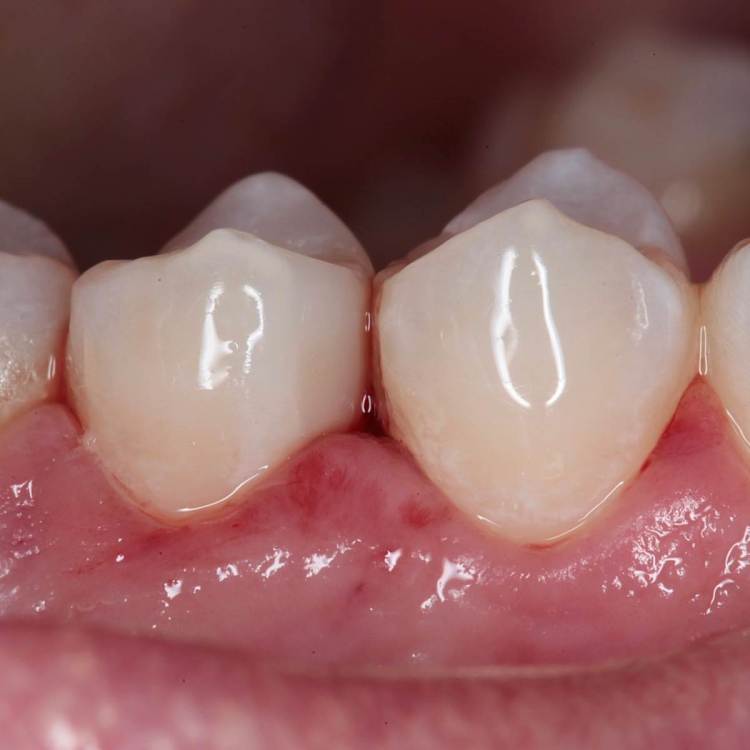

Как часто мы сталкиваемся с такими процессами и как редко пациент сам предъявляет какие то жалобы на такие зубы. Максимум это… застревание пищи.

Глубина полости ниже уровня десневого края на 2-3 мм. Коагуляция, ENDO, анатомичный билдап, проверка качества реставрации и отсутсвие нависающего края (интерпроксимальный снимок), рекомендации.

На следующий день никаких жалоб.

Эндо 25.06, 40.04, 60.02. Обтурация инжекторной техникой. Восстановление гармонайз а3 и желтая текучка от эстелайта (говорят ее сняли с производства, жаль, очень классный материал был)